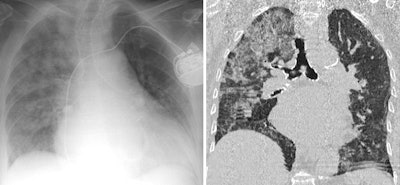

In this case of atypical pulmonary edema, predominant left-sided edema is due to acute mitral valve rupture with eccentric regurgitation seen at echocardiography. Bilateral pleural effusion is also seen. All images courtesy of Dr. Juan Arenas-Jiménez, PhD.

An 89-year-old woman presented with dyspnea and elevated D-dimer. Cardiomegaly and marked elevated proBNP suggested the diagnosis of unilateral pulmonary edema that resolved after diuretic treatment. D-dimer levels are elevated in most patients with acute thrombosis, but the levels also are increased in advanced age, after surgery, during pregnancy and puerperium, with cancer and other chronic inflammatory conditions, and in many other disorders. D-dimer elevation is the cause of request for many CT angiograms that finally reveal an alternative diagnosis causing dyspnea.On drug toxicity, the group suggests always bearing in mind treatment-related reactions, especially in patients with neoplasms, connective tissue, and transfusions. These reactions can appear in recently initiated or long-standing treatments.